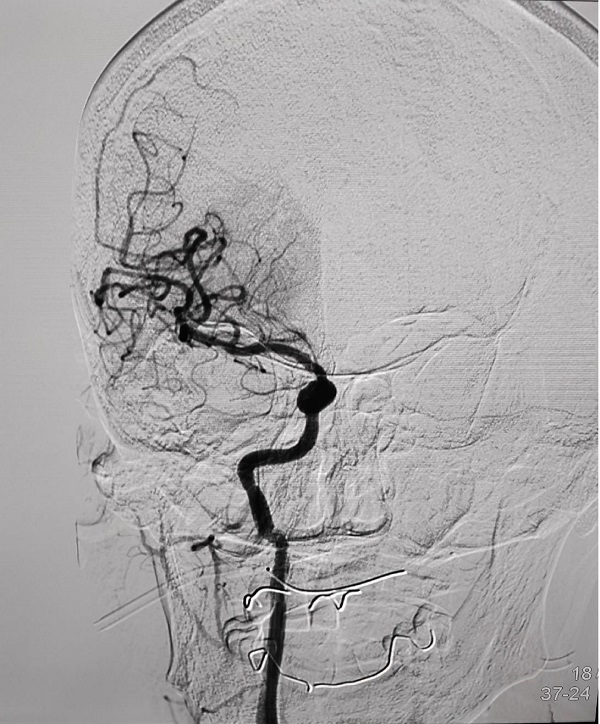

CTP检查结果提示,姬阿姨颅内核心梗死体积约9.6ml(红色区域),但低灌注区域体积高达81ml(绿色区域)(图2),低灌注区域越大,代表可挽救的脑神经细胞越多,手术开通的价值越大,可见患者颅内低灌注区域远远大于核心梗死区域,颅内动脉取栓术手术指征进一步明确。在与患者家属积极沟通,征得家属同意后,王建峰主任团队在国家级高级卒中中心李健主任的指导下,急诊进行了全脑血管造影术+颅内动脉取栓术,术中证实右侧大脑中动脉起始段闭塞(图3),并急诊进行了右侧大脑中动脉取栓术,术中抽拉出一块暗红色血栓,术后可见右侧大脑中动脉血流通畅(图4)。术后1周,在神经内科一病区医护人员的精心照料下,姬阿姨完全康复,说话言语清晰,对答切题流畅,四肢肌力活动恢复正常,现已康复出院。

图2